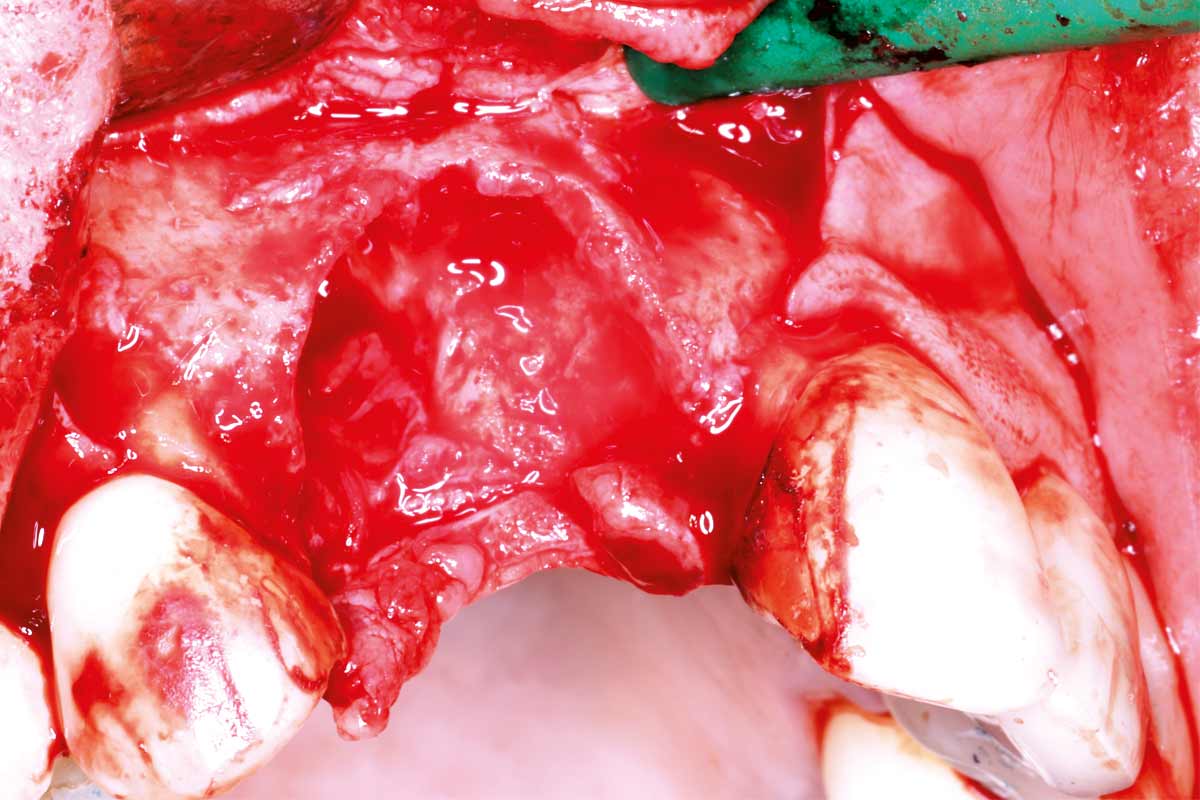

03/10 - Flap elevation, exposition of the defect which reach the apex of 12 and 11Maxillary bone reconstruction in the anterior area with cerabone® and Jason® membrane - Dr. P.-Y. Gegout & Prof. O. Huck

04/10 - Ridge defect after the extraction of 11 and 12Maxillary bone reconstruction in the anterior area with cerabone® and Jason® membrane - Dr. P.-Y. Gegout & Prof. O. Huck